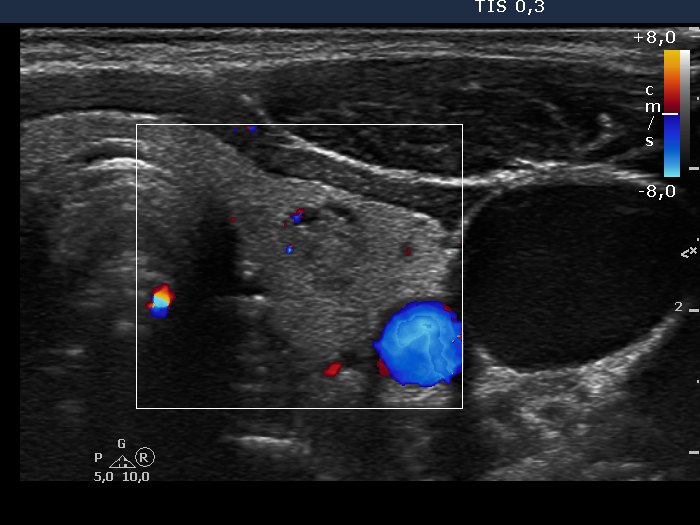

Study on extrathyroidal spread of papillary carcinoma - Case 2. (ultrasonographic picture 10)

Left lobe, horizontal scan, color Doppler mode.